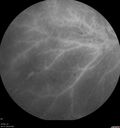

Traumatic Peripapillary Subretinal Hemorrhage2 views16 year old hit in eye with finger during basketball. Vision is 20/25 and there is a peripapillary hemorrhage.Apr 13, 2026